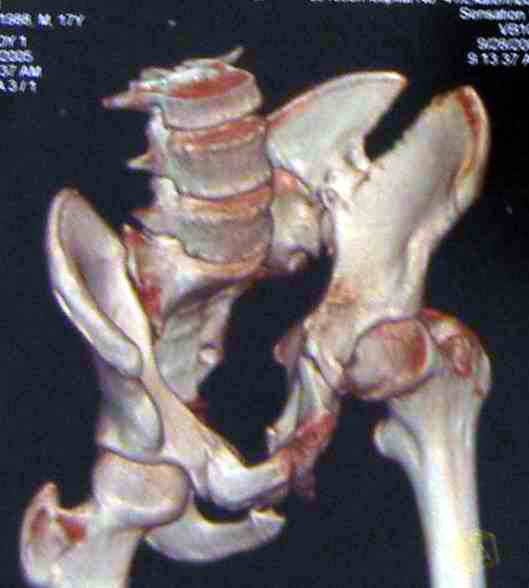

Коллеги, помогите определиться с тактикой лечения пациента. Ув. коллеги, к нам поступил молодой человек 17 лет. Травма в июле 2005- ДТП, т.е. 3 мес назад. Лечился консервативно в "гамаке" 1,5 мес., затем ходьба с костылями без опоры на левую нижнюю конечность, начал на нее опираться 1 нед назад. В настоящее время имеется укорочение порядка 4-5 см, выраженная хромота, передвигается с одним костылем. Кроме того беспокоят боли в пояснично-крестцовой области при ходьбе, неудобство при сидении, невозможность лежать на спине "на жестком", а также на левом боку (субъект худощавый, боль в области крыла) хромота, длительное пребывание на ногах невозможно. На функциональных снимках большой подвижности нет (не привожу из-за плохого качества). Учитывя наличие участков сращений, помогите опредилиться с тактикой. Наш план пока такой: 1. выполнить остеотомии в участках сращений 2.постепенно аппаратом низвести смещенную половину таза. 3.выполнить внутренний остеосинтез передних и задних отделов. Будем признательны за ваш взгляд на тактику леченияэтого больного, а так же на такие проблемы как: места остеотомий, возможные варианты компоновки аппарата, выбор имплантатов для последующего вмешательства.

Уважаемый коллега. Не знаю, прооперировали-ли вы больного или нет, но глядя на Р-граммы захотелось поделится сосбражениями. Укорочение конечности на 4-5 см конечно-же нужно устранить. Вы хотите выполинть остетомию мест сращения, любопытно каким образом? Если пользоваться широкими доступами, то возможно выпонить репозицию открыто и фиксировать погружнными конструкциями как Вы и планируете после репозиции в аппарате. Тем самым устранить укорочение конечности, может быть конечно не оплностью но на 2-3 см то точно. Закрыто же выполнить остеотомию сращений наверное возможно сзади, спереди я бы не рискнул, а лонные кости рубить надо. Что касается лечения аппаратом, то я ученик "вашей школы" что вашим аппаратом можно устранить смещения полностью. Но стоит ли подвергать пациента длительному дискомфорту и повышать риск воспалительных осложнений? Учитывая Ваш опыт лечения таких повреждений таза я бы остановился на одномоментной открытой репозиции и остеосинтезе. С уважением Гринь Алексей.